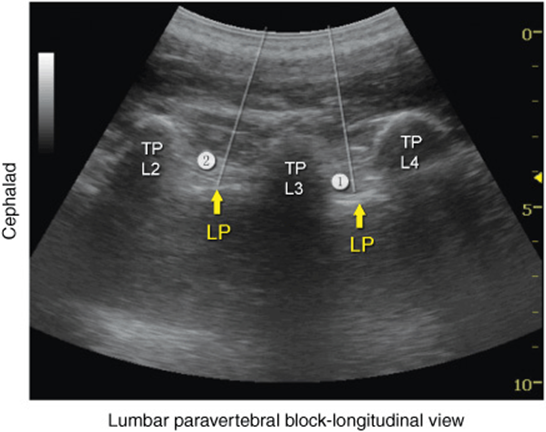

More recently, Karmakar and colleagues described the “trident sign technique,” which uses an easily recognizable ultrasonographic landmark, transverse processes, and an out-of-plane needle insertion. The trident sign technique derives its name from the characteristic ultrasonographic appearance of the transverse processes (trident) to estimate the depth and location of the lumbar plexus. After application of ultrasound gel to the skin over the lumbar paravertebral region, the ultrasound transducer is positioned approximately 3 to 4 cm lateral and parallel to the lumbar spine to produce a longitudinal scan of the lumbar paravertebral region (Figure 46-7). Then the transducer is moved caudally, while still maintaining the same orientation, until the sacrum and the L5 transverse process become visible (Figure 46-8). The lumbar transverse processes are identified by their hyperechoic reflections and acoustic shadowing beneath which is typical of bone. Once the L5 transverse process is visible, the transducer is moved cephalad gradually, to identify the L3-L4 level. The goal of the technique is to guide the needle through the acoustic window between the transverse processes (between the “teeth of the trident”) of L3-L4 or L2-L3 into the posterior part of the psoas major muscle containing the roots of the lumbar plexus (Figure 46-2B). After obtaining ipsilateral quadriceps muscle contractions, the block is carried out using the previously described injection and pharmacology considerations (Figures 46-9 and 46-10).

FIGURE 46-9. Simulated needle insertion paths (1,2) to inject local anesthetics at two different levels to accomplish a lumbar plexus (LP) block. Needles (1 and 2) are seen lodged about 2 cm deeper and between the transverse processes (TPs) using an out-of-plane technique.